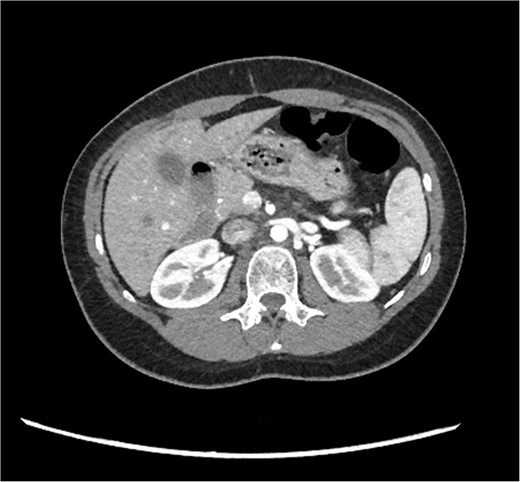

A 29-year-old female, with a past medical history of asthma and anxiety, presented to A&E Department at Mater Dei Hospital in view of a 2-day history of worsening right-sided colicky flank pain that radiated down to the right iliac fossa. Pain relief, including paracetamol and NSAIDS, alleviated her symptoms temporarily; however, pain recurred after a few hours. At A&E, patient’s parameters were noted to be stable throughout the review. On examination, the patient’s abdomen was noted to be soft with tenderness over the right flank. No guarding was noted, and renal punch was negative bilaterally. Blood investigations were all within normal limits, and urinalysis was normal. In view of the examination findings, a computed tomography (CT) of the kidney, ureters, and bladder was ordered, which noted an enlarged pancreatic head measuring 3 cm in diameter with noted upstream atrophic changes in the body and tail with fat stranding; prominent mesenteric lymph nodes were also noted. Based on the previous CT findings, a contrast CT of the pancreas was ordered, which revealed that the body and tail of the pancreas were absent; however, the pancreatic head was noted to be enlarged. This can be seen in Figs 1 and 2. Prominent lymph nodes with ground glass changes in the mesenteric fat were noted. CT pancreas therefore confirmed the diagnosis of dorsal agenesis of the pancreas. The patient was discharged home on pain relief and an outpatient’s appointment with the hepatobiliary team. Upon review at outpatients, the patient was well. She noted that she had been complaining of intermittent right loin pain over the past 3 years. Over the 2 months from review at A&E, the patient was well and denied further abdominal pain. In view of this, the patient was reassured and discharged. She was advised to seek medical advice should symptoms recur.

CT pancreas demonstrating absent body and tail of pancreas in coronal view.